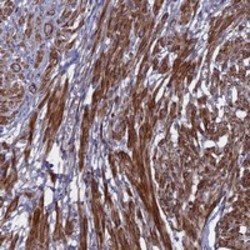

- Immunohistochemical staining of human smooth muscle with FAM209A polyclonal antibody (Cat # PAB23974) shows strong cytoplasmic and membranous positivity in smooth muscle cells at 1:20-1:50 dilution.

- Immunohistochemistry (Formalin/PFA-fixed paraffin-embedded sections)